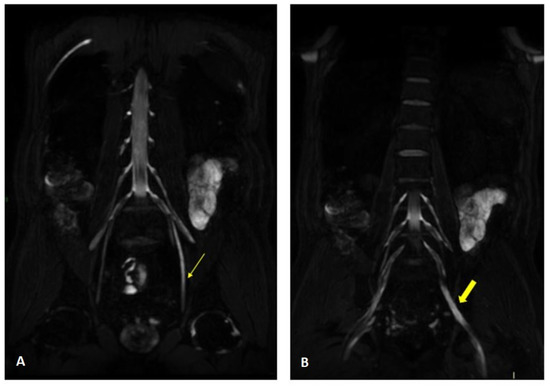

Figure 3.

MIP (Maximum Intensity Projection) reconstructions of the 3D cube nerve MR sequence of the brachial (A) and lumbosacral (B) plexus showing a pathological and asymmetric thickening and increase in T2 signal representation of them.

Figure 4.

MR 3D cube nerve images show thickening and T2 hyperintensity of the left obturator nerve (thin arrow in A) and lumbosacral trunk (thick arrow in B) compared to the contralateral one (transverse diameter on left L5 root 7.7 mm (n.v. * 5.99 ± 0.66) and on left S1 root 9.1 mm (n.v. * 5.27 ± 0.53). * Normal values (n.v.) according to the recent study of Su X et al. [20].